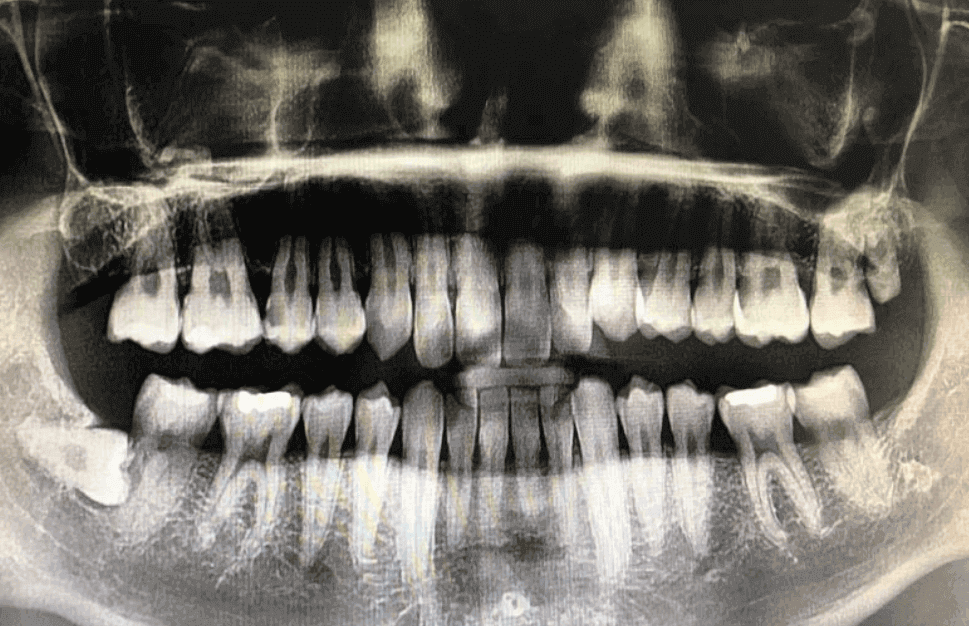

제 현재 상태는 아래와 같습니다.

필요치료 : 임플란트 5개 / 크라운 1개 / 신경치료 2개 / 브리지 1개 / 충치치료 1개

치과 선정 및 최초 상담 파노라마 엑스레이 비용 및 보험

파노라마 엑스레이는 대한민국 국민이라면 건강보험이 적용되는 부분이며, 금액은 병원마다 그리고, 복지가 다른 노인분들과는 차이가 있을 수 있지만 기본 성인 분들이라면 11,000 - 13,000원이 청구되며, 여기에는 기본적인 의사 선생님과 상담까지 포함됩니다.

치과 파노라마 엑스레이 : 건강보험 적용 가능, 11,000원 - 13,000원 실제 청구 비용 발생